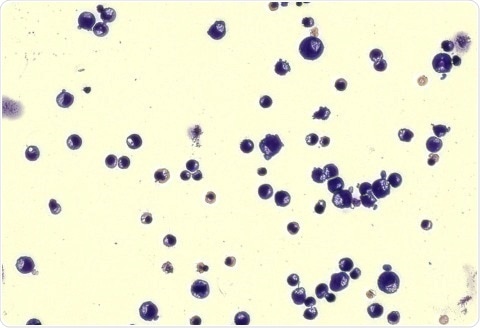

Image of stained erythroblasts, a nucleated cell in the bone marrow from which red blood cells develop. Image Credit: The Feinstein Institutes for Medical Research at Northwell Health